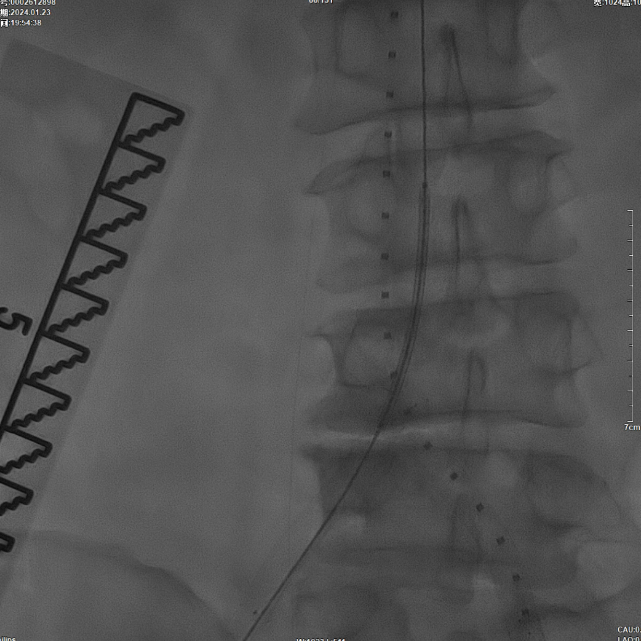

首先使用14mm球囊进行初步扩张,鉴于腹主动脉直径约15mm,最终选用16mm球囊进行扩张。

当扩张压力达10 ATM时,患者出现轻微疼痛,遂停止扩张。扩张前需将左侧导丝撤出,扩张后重新置入并确认导丝位于支架内。

该图解释为何远端距离双侧髂总动脉分叉至少1.5cm,以避免后扩张时大球囊对髂动脉造成损伤。